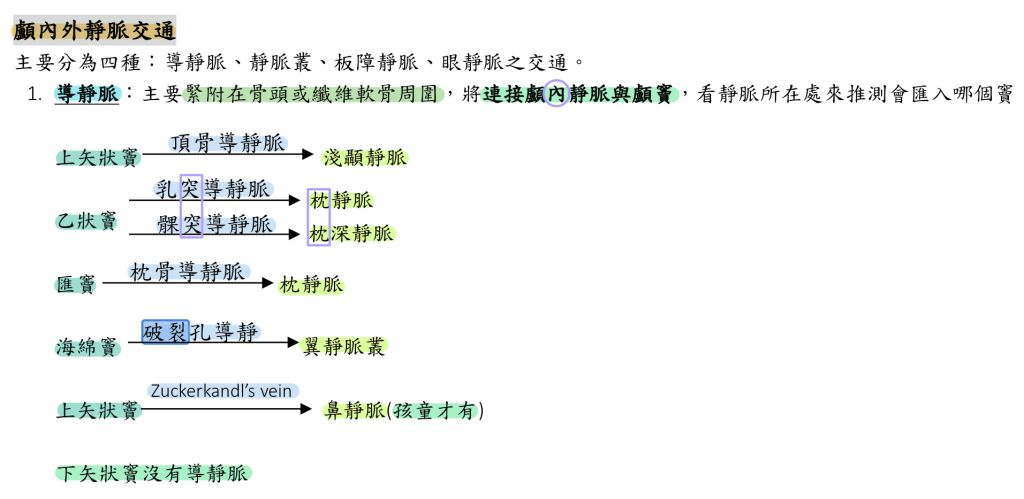

顱內